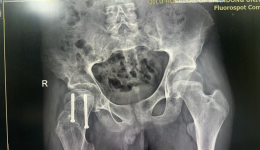

近日,山东大学齐鲁医院(青岛)小儿骨科迎来了一位不同寻常的患者——38岁的艾先生(化姓)。通常情况下,小儿骨科接诊的是青少年及儿童患者,而艾先生的到来,则是因为一种极为罕见且复杂的病症组合:垂体柄阻断综合征合并股骨头骨骺滑脱。艾先生...